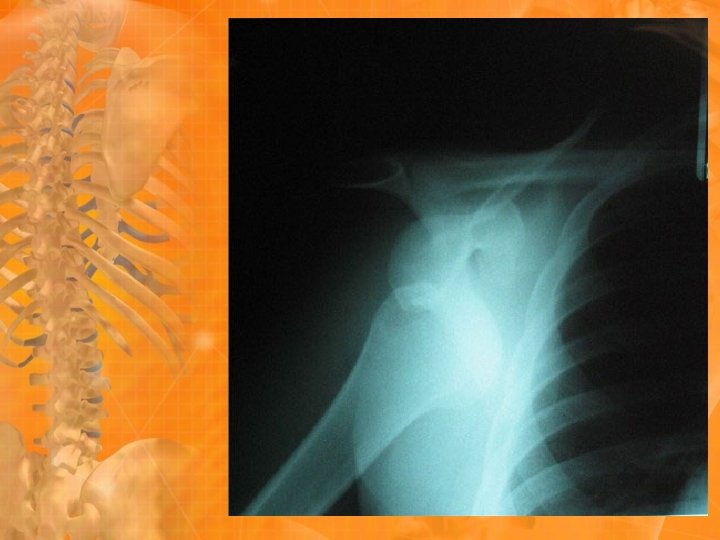

Synovial Joint Injuries 6. Subluxation • Partial separation between two articulating bones 7. Dislocation • Complete disunion between two articulating bones